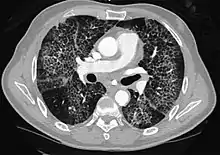

CT showing diffuse ground-glass opacities in periphery of both lungs in patient with COVID-19.

Ground-glass opacity is among the most common imaging findings in patients with confirmed COVID-19.[16][17] One systematic review found that among patients with COVID-19 and abnormal lung findings on CT, greater than 80% had GGOs, with greater than 50% having mixed GGOs and consolidation.[16] GGOs with mixed consolidation has most often been found in elderly populations.[18] Several studies have described a pattern among initial, intermediate, and hospital discharge imaging findings in the disease course of COVID-19. Most commonly, initial CT imaging reveals bilateral GGOs at the periphery of the lungs. During initial stages, this is most often found in the lower lobes, although involvement of the upper lobes and right middle lobe has also been reported early in the disease course.[16][18] This is in contrast to the two similar coronaviruses, SARS and MERS, which more commonly involve only one lung on initial imaging.[19][20] As the COVID-19 infection progresses, GGOs typically become more diffuse and often progress to consolidation.[11][18] This is sometimes accompanied by the development of a crazy paving pattern and interlobular septal thickening.[18] In many cases the most severe pulmonary CT abnormalities occurred within 2 weeks after symptoms began.[17] At this point, many individuals begin showing resolution of consolidation and GGOs as symptoms improve. However, some patients have worsening symptoms and imaging findings, with further increase in septal thickening, GGOs, and consolidation. These patients may develop lung "white-out" with progression to acute respiratory distress syndrome (ARDS) requiring treatment escalation.[17][21]

Preliminary reports have shown many patients have residual GGOs at time of discharge from the hospital. Due to the novelty of COVID-19, large studies investigating the long-term pulmonary CT changes have yet to be completed. However, long-term pulmonary changes have been seen in patients after recovery from SARS and MERS, suggesting the possibility of similar long-term complications in patients who have recovered from acute COVID-19 infection.[22]